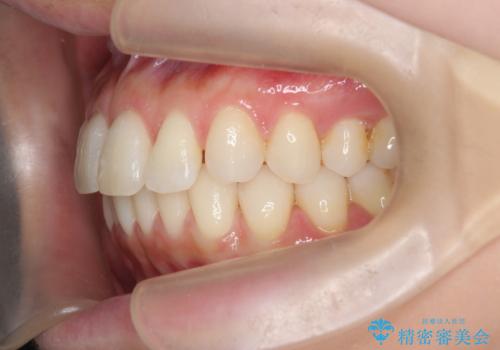

昔ワイヤー矯正をして後戻りした 軽度のがたつき モニター矯正

- 矯正治療後の後戻りを主訴に来院。

特に下の前歯のがたつきを気にされていました。

マウスピース矯正で再矯正を行いました。

再度の後戻りを防ぐため、下顎前歯の裏にはワイヤーを貼る保定を行っています。